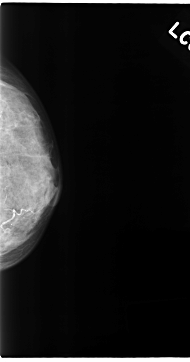

C_0125_1.LEFT_MLO

LEFT_MLO LINES 4720 PIXELS_PER_LINE 2504 BITS_PER_PIXEL 12 RESOLUTION 50 NON_OVERLAY